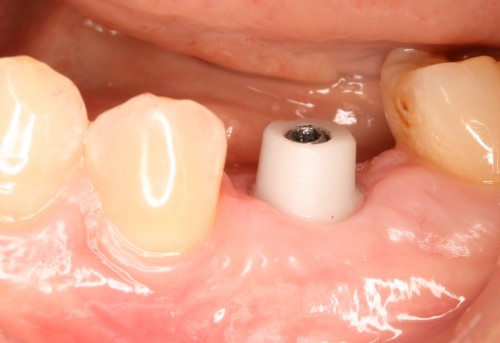

術前

インプラント挿入

土台装着

被せ物装着

同パノラマ写真

被せ物装着後歯肉の盛り上がり